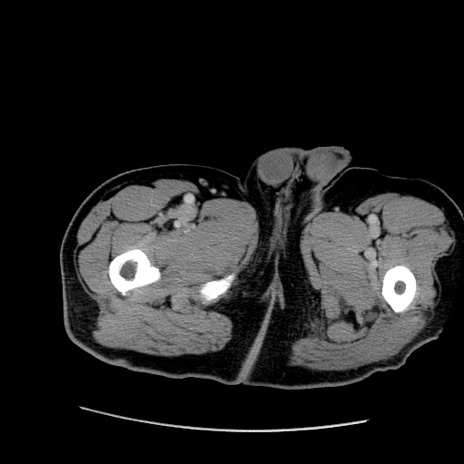

症例22(横断像)

【症例】50歳代男性

【主訴】腹痛

【現病歴】AVMからの被殻出血のため回復期リハ病棟入院中。 本日午後3時頃急に下腹部痛が出現した。

【既往歴】AVM、被殻出血、虫垂炎、高血圧

【身体所見】意識晴明、左半身不全麻痺、会話の理解は良好、36.5°C、腹部:膨隆、全体に板状硬、下腹部正中に圧痛点あり、反跳痛-、筋性防御不明、右下腹部にope scar

【データ】WBC 9400、CRP 0.06